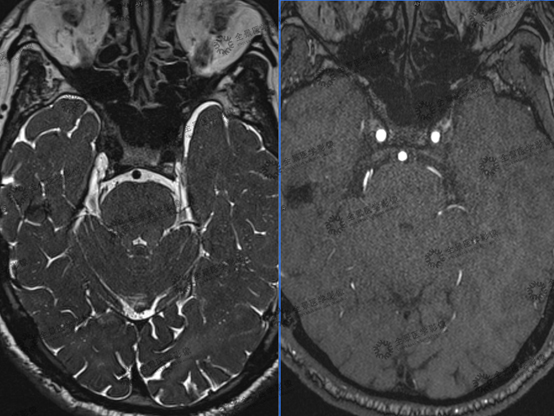

上海全景医学影像诊断中心利用西门子3.0T高场强磁共振扫描仪,采用MRTA序列为:3D TOF MRA序列联合T2 space序列,利用融合校准技术,形成多模态融合MRTA图像,可做到简化阅片,同时可以清晰显示三叉神经与责任血管的解剖关系,明确责任血管来源,并可以利用三维重建进行空间定位,对临床进行术前诊断、术前评估和指导手术方案具有重要的意义。

病史:患者,男,74岁,右侧面部疼痛7年,临床诊断:右侧三叉神经痛